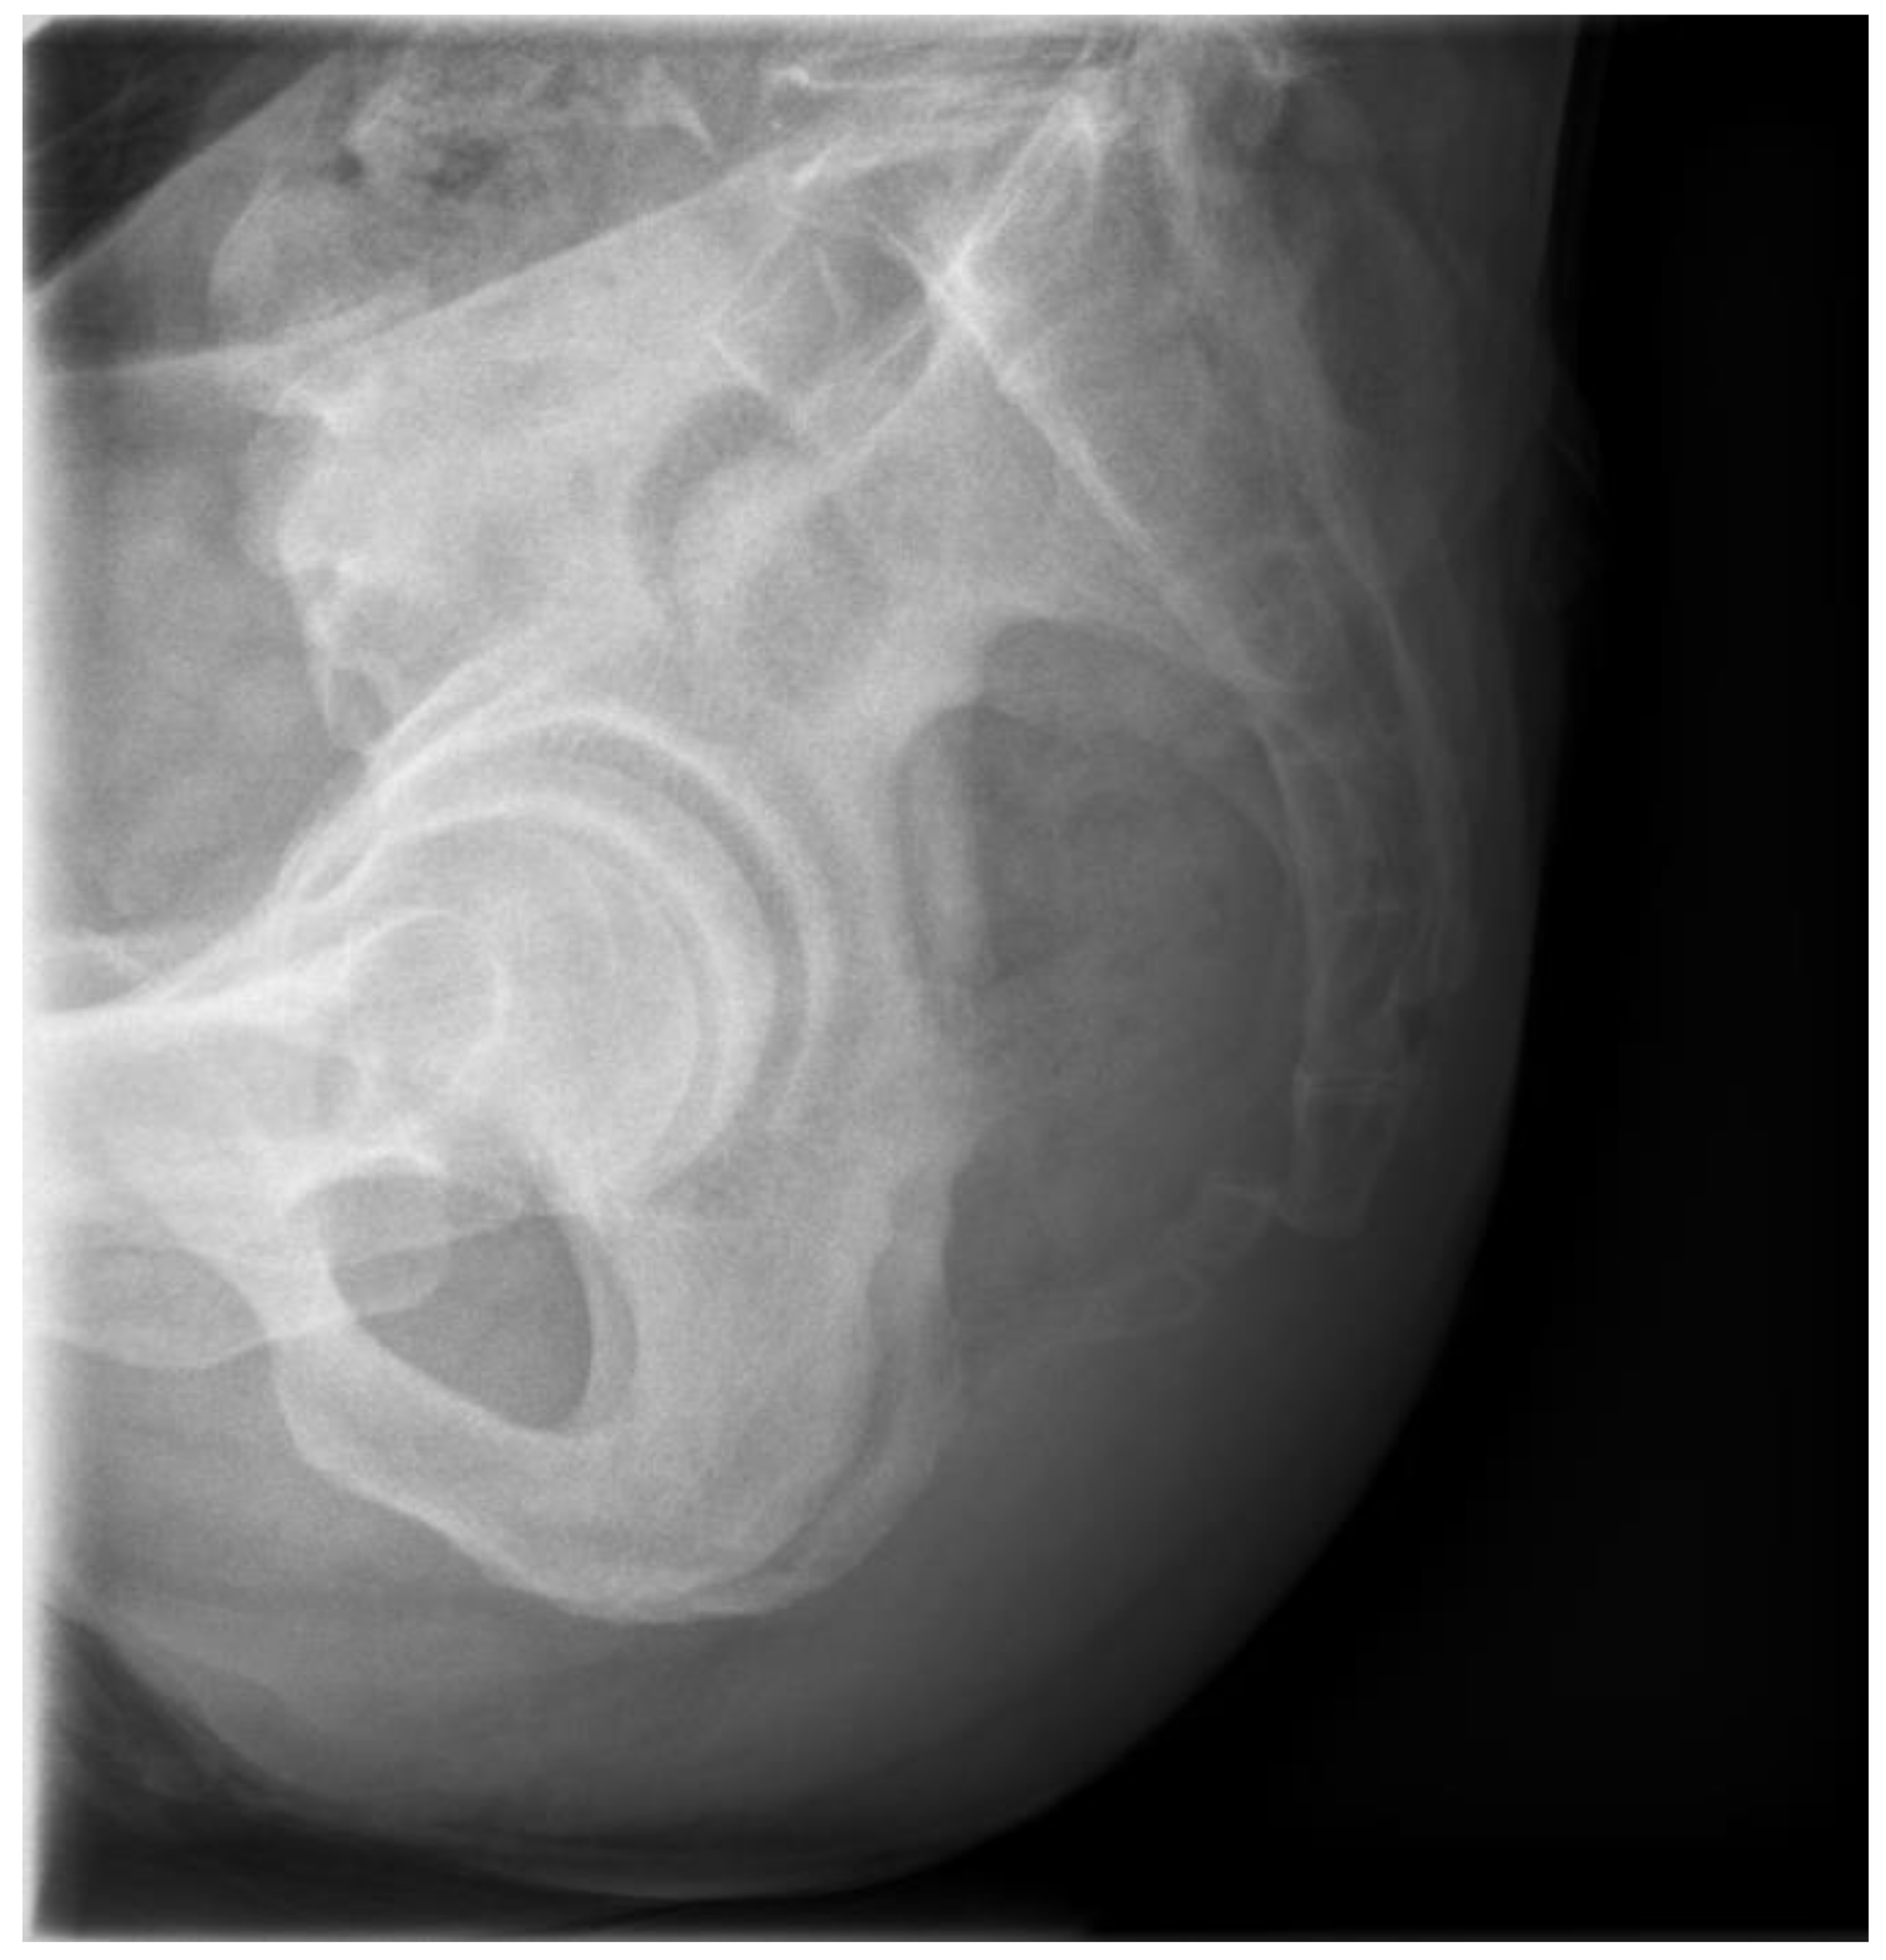

A 56-year-old male patient presented to the outpatient clinic three days after experiencing coccygeal pain due to a backwards fall. He complained of severe tenderness in the coccygeal area, but no bruising or external wounds were observed. No significant signs of neurological injury were detected. The patient had no underlying disease except hypertension. On plain radiography, the coccyx was anteriorly dislocated from the sacrococcygeal joint (Figure 1).

Figure 1. Initial plain lateral radiography shows anterior dislocation of the coccyx.